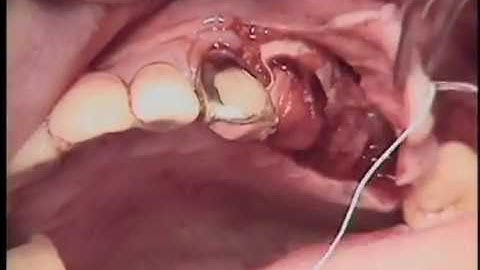

Horizontal Ridge Augmentation with Ti Mesh and Simultaneous Implant Placement